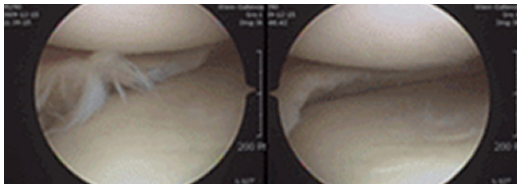

관절 내시경으로 본 정상 십자인대

전방 십자인대파열

십자인대는 무릎의 앞뒤 움직임을 제어하는 중요한 구조로, 축구, 스키 같은 운동이나 넘어지며 비틀릴 때 손상될 수 있습니다.

십자인대가 파열되면 자연 치유가 어려운 경우가 많으며, 평균 7~10년이 지나면 연골 손상과 관절염이 발생할 수 있습니다.